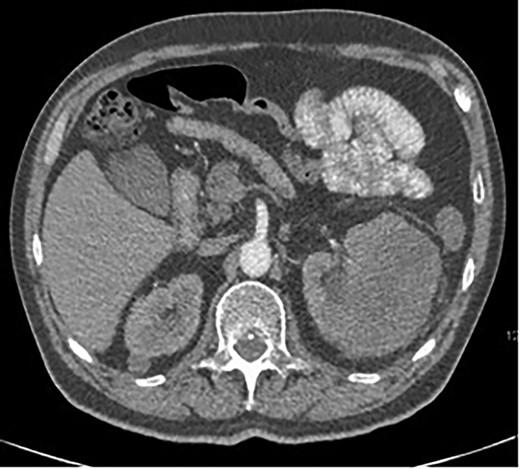

A 63-year-old male with a medical history of hypertension and progressive dyspnoea on exertion, underwent a computed tomography (CT) angiogram for the workup of a pulmonary embolism. There was an incidental finding of a 12-cm left renal neoplasm (Fig. 1), extensive metastatic nodal abdominal disease and bilateral metastatic pulmonary disease (T3 N2 M1). He was discussed at the Urology multidisciplinary team meeting (MDT) and commenced on Sunitnib, given the dissemination of disease. Repeat imaging showed a significant reduction in size of the pulmonary metastasis. Following which, he underwent a cryo-reductive nephrectomy that confirmed a clear cell RCC 102 mm, Grade 3. Development of a tongue lesion after a year warranted Otorhinolaryngology input. Clinical assessment with flexible nasendoscopy depicted a 0.5 cm by 0.5 cm pedunculated lesion on the midline of the tongue (Fig. 2). A biopsy under local anaesthetic confirmed a clear cell RCC (Fig. 3) that was positive for AE1/AE3, Vimentin (Fig. 4) and EMA. Further CT imaging, 1 month after the biopsy confirmed left hilar nodule progression from 2.3 to 3 cm. The medical oncology MDT recommended commencing Nivolumab. Following recurrent bleeding from the tongue, radiation to the area was determined to be the best treatment modality. The patient is still clinically well and tolerating oral intake with no significant large bleeds to date. Regular medical oncology, radiation oncology, urology and Otorhinolaryngology follow-up is ongoing, however, the prognosis is poor with such disseminated disease and the primary focus is on minimising morbidity.

Axial CT showing a large 12-cm left renal heterogenous mass; no renal obstruction, hydronephrosis or calculus; the mass abuts the lower edge of the spleen.